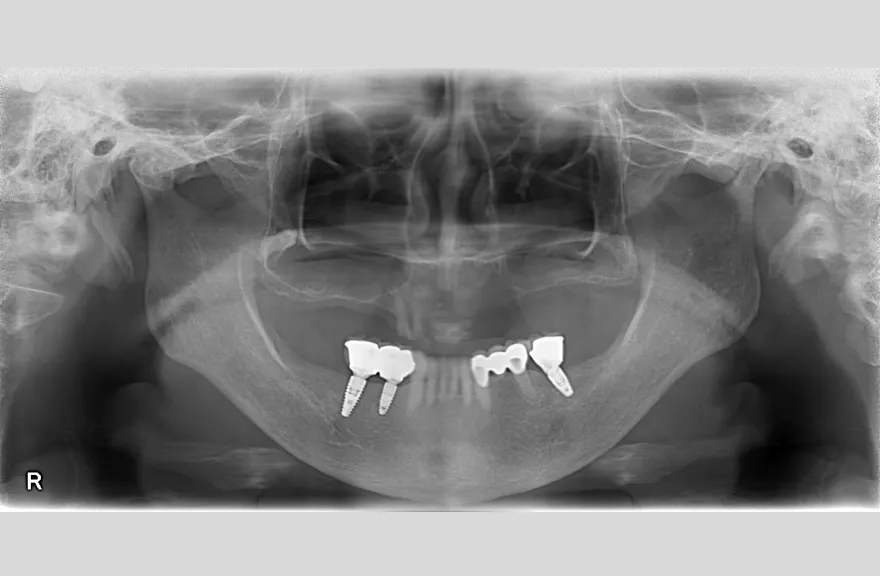

骨格の前後的な差がある方でした。術前のレントゲンより、上下で歯牙の損傷に明らかな差があるのがみてとれます。

上の歯がないところにインプラント治療を行い、上顎は全てインプラントフィクスチャーによる固定性の歯を入れられることも費用的には可能な方でした。

今回の症例では、敢えて上顎は総義歯形態をとり、骨格的な前後の差を解消するよう工夫しました。

上顎の残っていた歯も、差し歯としては使えずとも、敢えて根だけ残すことによって組織を温存し、義歯の安定に寄与するよう設計しました。

レントゲンをよく見るとお分かりいただけるかと思いますが右下の奥歯のインプラント(レントゲンでは左右逆にうつるので、左下)が既にインプラント周囲炎になっていました。

本当に治療をやり切ってしまうなら、右下の奥2本のインプラントを抜去、新しいインプラントフィクスチャーを埋入すべき症例でした。

しかし、患者さんとの話し合いで、「まだ使えるインプラントは置いておこう」ということになり、右下のインプラントは置いたまま治療を行っています。今後の人生の中で腫れたり痛む可能性があることは重々ご承知いただいております。